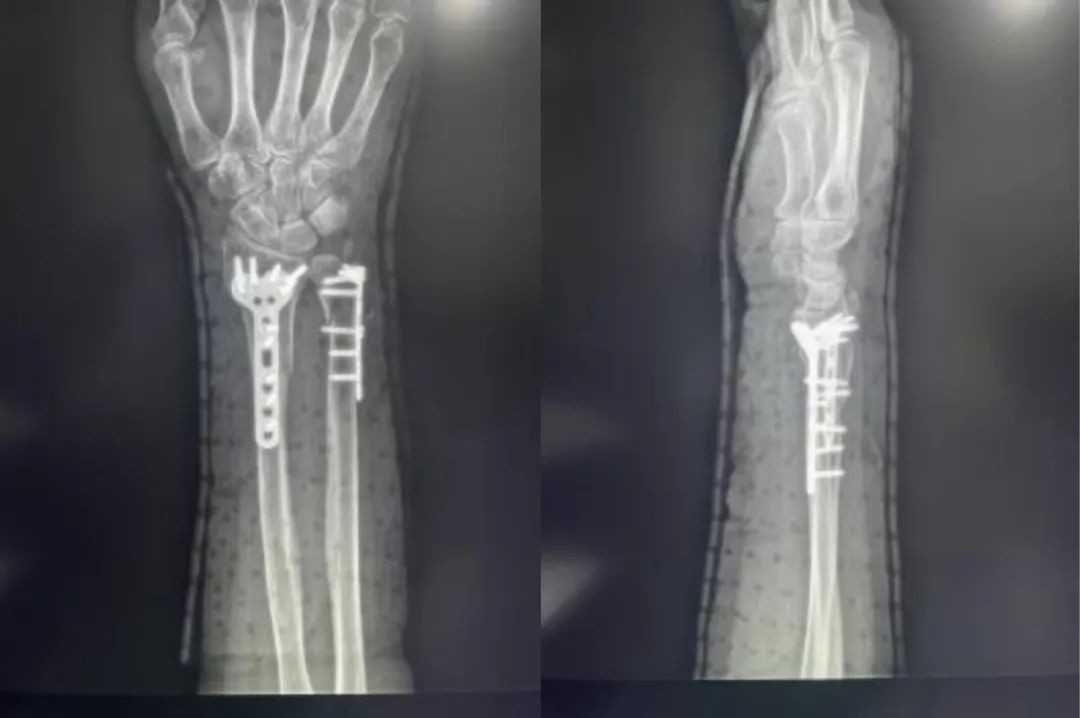

Distal radius fractures account for 75% of forearm fractures and are particularly common in the clinic. In this article, we have compiled a list of anatomy, classification, treatment strategies, and surgical approaches to distal radius fractures for your reference.

Case ①

Case ②

Case ③